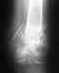

Здравствуйте! Моей дочке 2 года. 27июля она получила травму – перелом костей предплечья ср/3 со смещением. Гипс сняли 22 августа. Снимок показал, что признаки перелома остаются, сформирована костная мозоль. Скажите, когда косточки полностью срастутся? Будут ли последствия или все заживет бесследно? И еще – многие знакомые говорят, что у таких маленьких детей переломов не бывает, что дети очень гибкие?! Может нам нужно пройти обследование, сдать какие –то анализы?